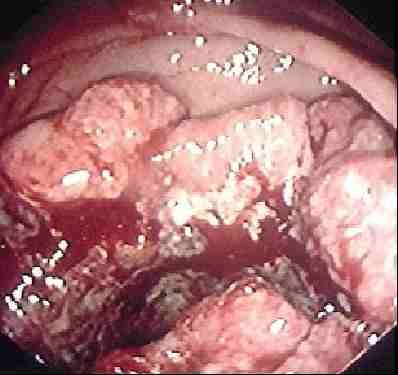

Un nuevo estudio, publicado en Cancer Cell, identifica una molécula que es, posiblemente, responsable del desarrollo y progresión del cáncer colorrectal y sugiere que esta molécula podría ser el objetivo de terapias dirigidas y un biomarcador para controlar la progresión del tumor. Para el estudio, los investigadores de la Universidad de Ohio (EEUU) utilizaron un modelo murino con cáncer de colon basado en la pérdida de un supresor tumoral, un modelo murino basado en la inflamación y la activación de un oncogen, tumores humanos de una cohorte de cáncer colorrectal esporádico y asociado a una enfermedad inflamatoria intestinal y datos del Atlas del Genoma del Cáncer. En el trabajo, descubrieron que la molécula microARN-135b (miR-135b) está presente de forma anómala en unos niveles altos en los tumores humanos y murinos. Esta sobreexpresión puede ser provocada por mutaciones en los oncogenes o los genes supresores de tumores que tienen lugar frecuentemente en este tipo de cáncer, según los investigadores.El estudio también revela que la alta regulación sucede tanto en los tumores esporádicos como asociados a la enfermedad inflamatoria intestinal y está asociada con el estadio del tumor y los malos resultados clínicos. La pérdida del gen APC, la desregulación de la vía PTEN/PI3K y la sobreexpresión del oncogen SRC provocan la sobreexpresión de miR-135b. Por otra parte, los investigadores descubrieron que la sobreexpresión artificial de miR-135b aumenta la proliferación celular y reduce la apoptosis, como sucede con la pérdida de APC o la activación de PI3K o SRC. Además, suministrar anti-miR-135b en un modelo murino con cáncer colorrectal asociado con la inflamación afectaba a la proliferación y la apoptosis, lo que provocaba una reducción tanto del tamaño como del número de los tumores.